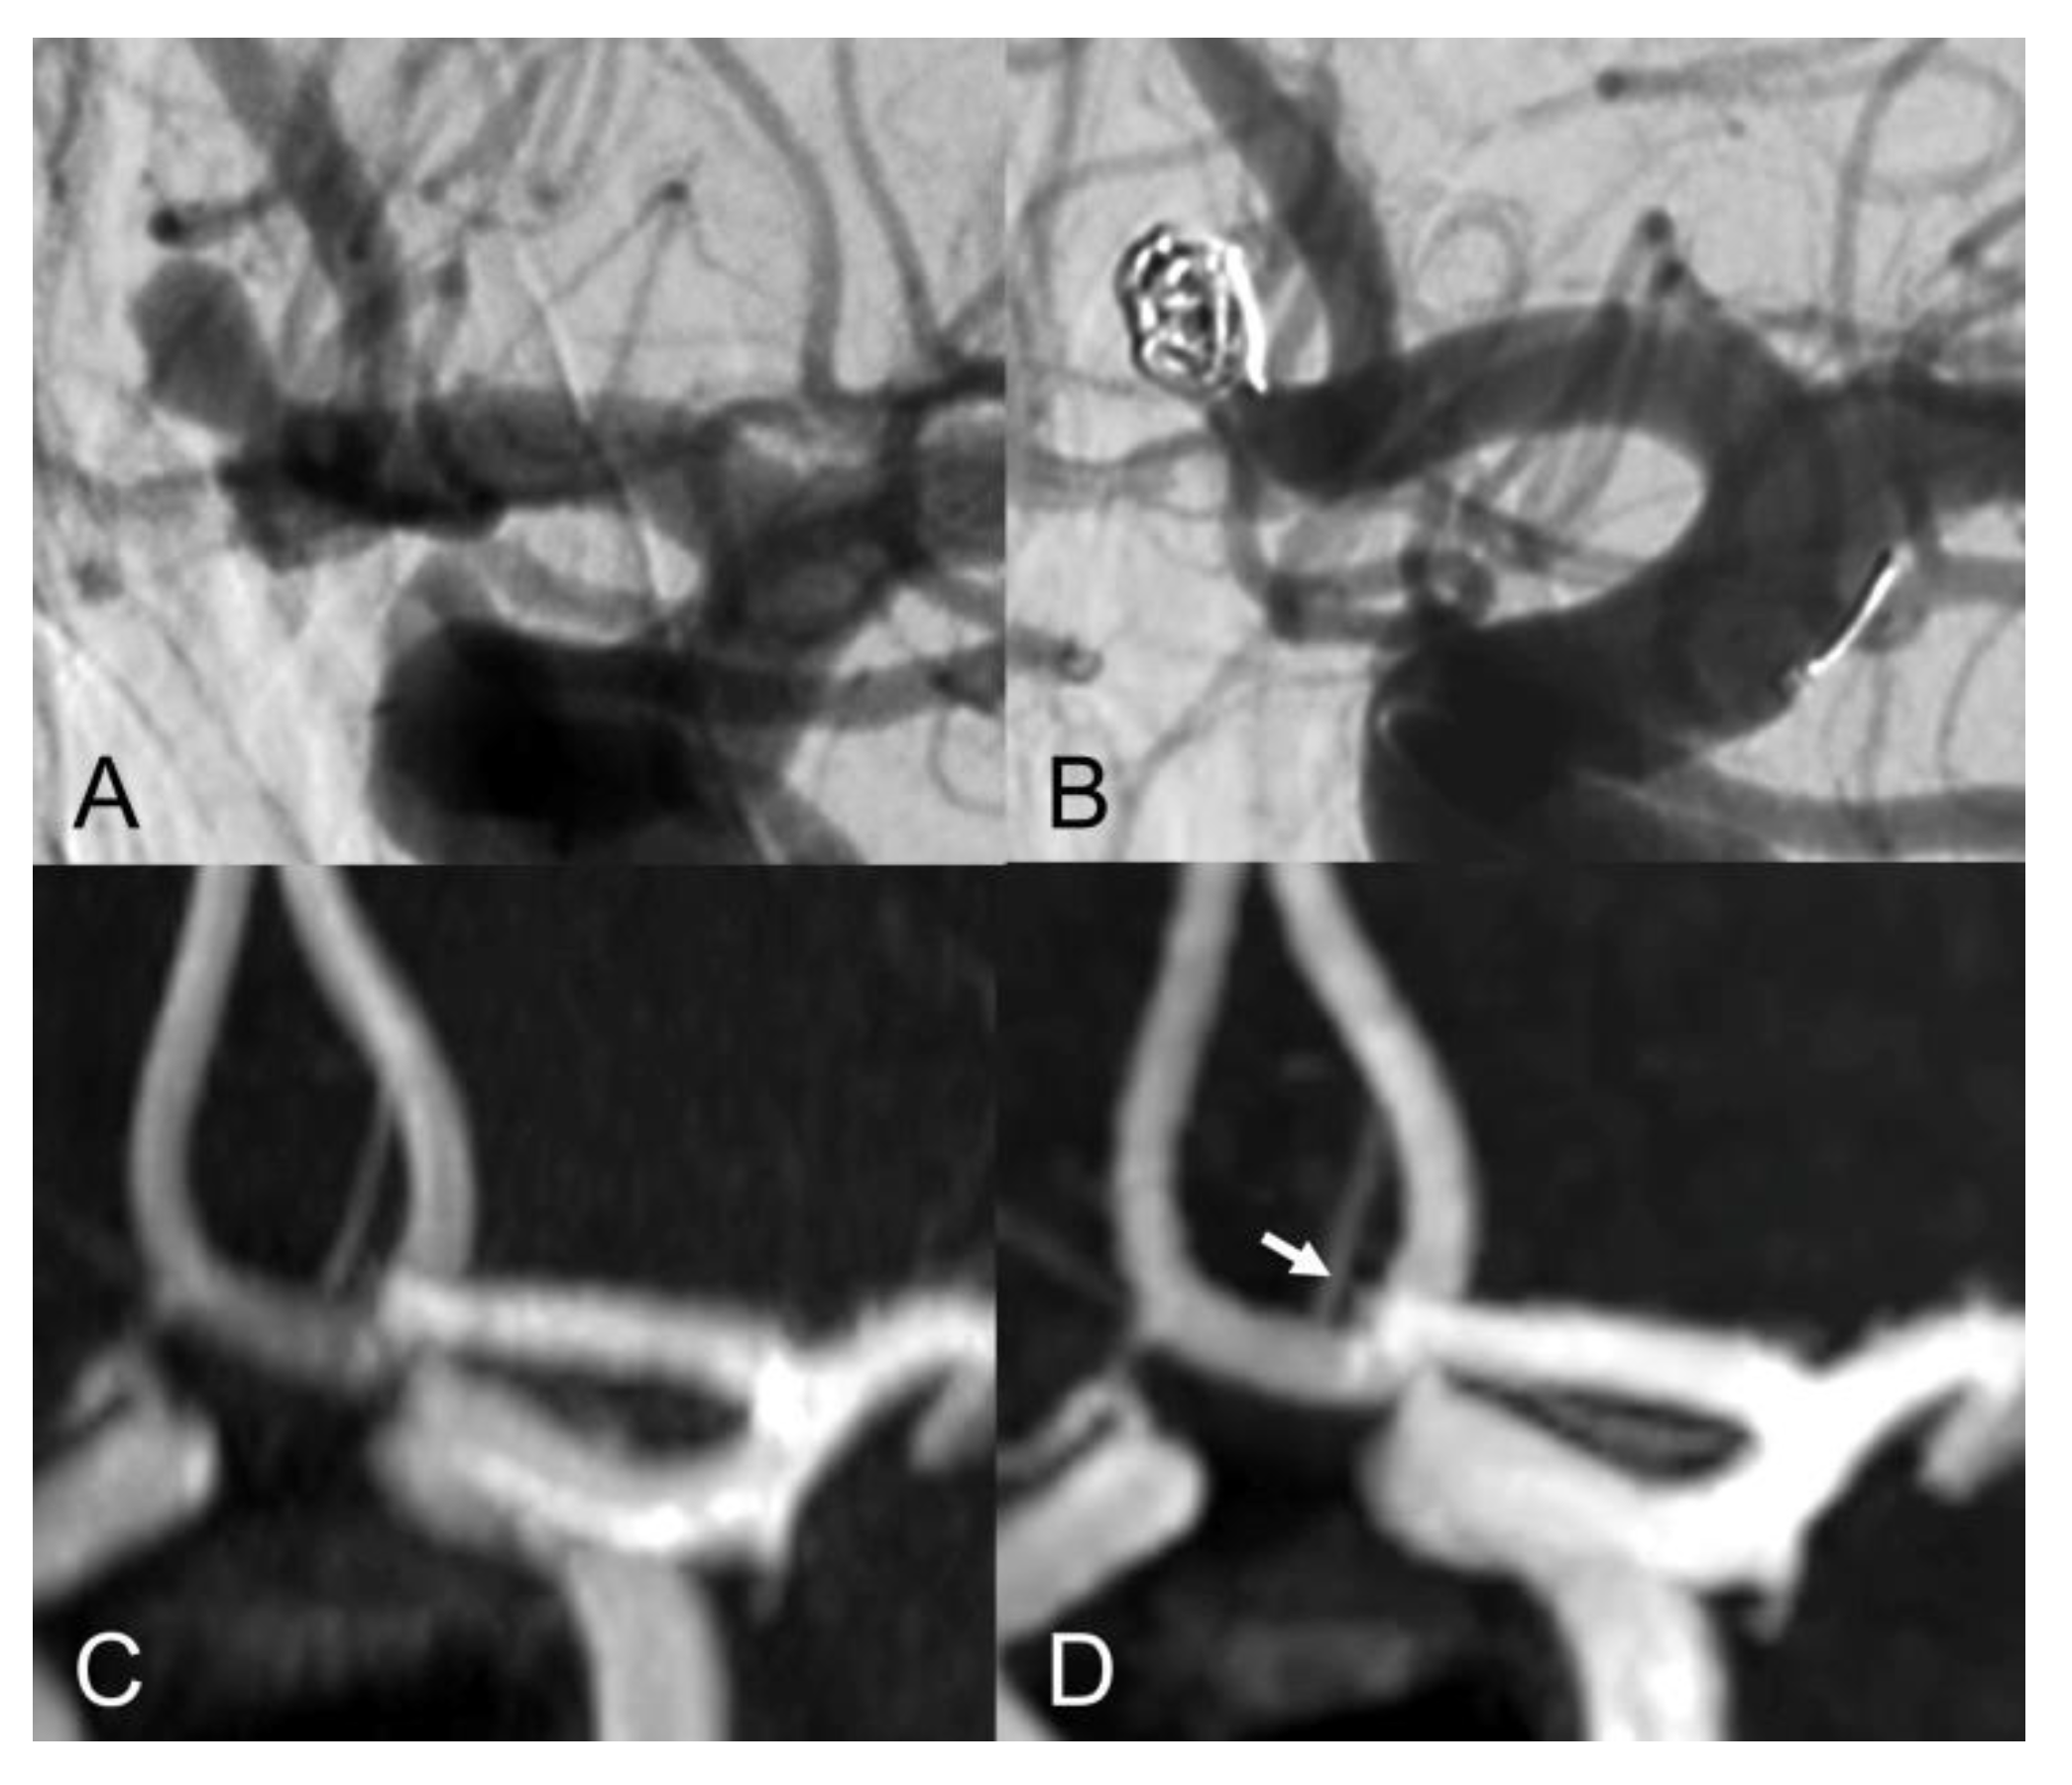

The evaluation of Class I - III coiled aneurysm occlusion status, with CS and PI TOF, is exemplified in Figure 1, Figure 2 and Figure 3.

Figure 1.

Anteroposterior view of vertebral artery digital subtraction angiography (DS) with (A) and without subtraction (B) after basilar-tip aneurysm coiling. Coronal MIP images of CS TOF (C) and PI TOF (D) showing complete occlusion of the aneurysm (class I). The interface between blood flow and coils is sharper on CS TOF images compared to PI TOF.

The inter-modality agreement of CS and PI TOF MRA in the evaluation of aneurysm occlusion was perfect (κ = 1.00, p < 0.001) for all examiners except one, which classified one anterior communicating artery aneurysm as Class I on PI TOF images and as Class II on CS TOF images (Figure 2), leading, nonetheless, to an almost perfect inter-modality agreement (κ = 0.90, p < 0.001). The overall inter-modality agreement between the two techniques, considering all the readings by all the examiners (n = 88) was almost perfect (κ = 0.98, p < 0.001). No significant differences in inter-modality agreement were noted between patients who underwent coiling and stent-assisted coiling (κ = 1.00 and κ = 0.97, respectively). The overall inter-rater agreement was substantial (κ = 0.70, p < 0.001) and was almost identical for both CS TOF (κ = 0.71, p < 0.001) and PI TOF MRA (κ = 0.68, p < 0.001); 12 aneurysms (54.5%) were evaluated by all the examiners as completely occluded on both MRA techniques.

Our findings are in agreement with previous studies which showed comparable results between CS TOF and PI TOF MRA in the detection of a variety of cerebrovascular pathologies, including aneurysms, stenosis and arteriovenous shunts [21,22,23,24,25]. In particular, no significant differences were found between CS TOF and PI TOF MRA in the depiction of intact aneurysms, as well as in the measurement of neck, height and width of aneurysms [22]. In our study, only one case received a different occlusion classification in CS and PI TOF images, by the neurointerventionalist reader, who correctly appreciated a small neck remnant in CS TOF images, which was not apparent in the PI sequence (Figure 2). Therefore, while magnetic susceptibility artifacts due to the presence of the coil cast seem to have a comparable effect on both sequences in the majority of cases, we observed a sharper interface between blood flow and surrounding coils in some CS TOF images compared to PI TOF counterparts (Figure 1, Figure 2 and Figure 3).